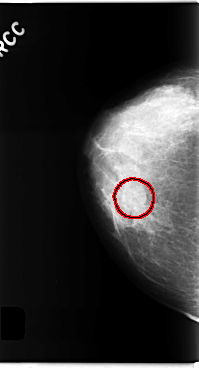

C_0284_1.RIGHT_CC

RIGHT_CC LINES 4784 PIXELS_PER_LINE 2576 BITS_PER_PIXEL 12 RESOLUTION 50 OVERLAY

FILE: C_0284_1.RIGHT_CC.OVERLAY

TOTAL_ABNORMALITIES 1

ABNORMALITY 1

LESION_TYPE MASS SHAPE ROUND MARGINS OBSCURED

ASSESSMENT 3

SUBTLETY 4

PATHOLOGY BENIGN

TOTAL_OUTLINES 1